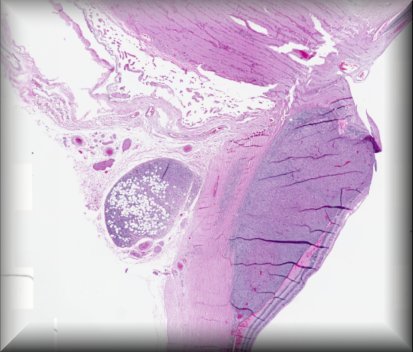

Thomas J. Cummings (Durham, North Carolina): 54-year-old male with multiple systemic infections underwent enucleation after 2 months of pain, redness and acute loss of vision. |